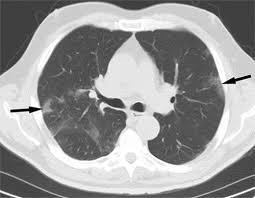

Pneumonia And Coronavirus Does Everyone With Covid 19 Get Pneumonia from img.webmd.com 1) infections with tb and other bacteria, 2) exposure to toxic and/or allergenic substances such as asbestos, 3) pulmonary fibrosis, and 4) autoimmune diseases like sarcoidosis. Aspergillosis, cryptococcosis, and mucormycosis are the most common opportunistic fungal infections that can mimic lung cancer. In addition, it isn't unusual for an infection to develop around a lung tumor, and the resulting pneumonia may obscure an underlying tumor. However, herrera says, if you. Common things are common ,pneumonia is lot common than lung cancer ,get an xray in 6 weeks it should clear up by then. Biopsy by surgery, bronchoscopy, or needle biopsy directed by a ct. 4, 5, 16, 17 of the patients with a history of nsclc, patients with a history of these 3 fungal infections from january 1, 2007, to may 1, 2020, were identified in starr using the addition of the following criterion. However, the symptoms of lung cancer differ vastly from bronchitis which is one of the commonest affections of chronic smokers.

Repeated respiratory infections, such as bronchitis or pneumonia, can be a sign of lung cancer. Furthermore, lung cancer symptoms, such as a persistent cough, back pain or weight loss, can resemble a cold or bronchitis and may not raise suspicions of lung cancer. Or, you might have a chest infection that doesn't get better with treatment. In addition, it isn't unusual for an infection to develop around a lung tumor, and the resulting pneumonia may obscure an underlying tumor. Lung cancer is a common cause of finger clubbing; Clinical and epidemiologic studies have suggested a strong associati … However, it can occur in other heart and lung diseases. Despite the importance of all the causes mentioned by the authors, we would like to emphasize the relevance of fungal infections as an important cause of pulmonary nodules and masses that can mimic lung. Pneumonia in people with lung cancer. The cancerous tumor (s) cause a decrease in normal lung cell functioning, which can block the airways of the lungs leading conditions susceptible to infections. However, the symptoms of lung cancer differ vastly from bronchitis which is one of the commonest affections of chronic smokers. Lung cancer most often spreads to the liver, the adrenal glands, the bones, and the brain. The test they may be considering is a pet scan.

This Woman Thought She Had Pneumonia But Had Lung Cancer Health Com from imagesvc.meredithcorp.io Lung cancer can also increase the risk of pneumonia by weakening the immune system. Lung cancer is the last thing a doctor thinks to look for in young, nonsmoking women, says gerold bepler, m.d., director of the comprehensive lung cancer research center at the moffitt cancer. Biopsy by surgery, bronchoscopy, or needle biopsy directed by a ct. In this article they describe a variety of pulmonary conditions that can present with imaging features mimicking those of primary lung cancers. The test they may be considering is a pet scan. In these cases, there is, in actuality, an infection in the body, but a cancer is the real, deeper culprit. Moreover, a lung infection further compromises the ability of the lungs to function properly. Or by inserting a tube through the chest wall to drain infection (thoracostomy).

According to roy castle lung cancer foundation (rclcf), a telltale sign your chest infection is cancerous is whether it persists. Lung cancer is an uncontrolled and uncoordinated overgrowth of the lung tissue. In this article they describe a variety of pulmonary conditions that can present with imaging features mimicking those of primary lung cancers. Cancer was the furthest thing from my mind, but lung cancer, i just couldn't believe it. she was only 39, she wasn't a smoker, she ate healthy, ran, and did yoga. This article is more than 7 months old. They can be a sign of lung cancer, however. Lung cancer can also increase the risk of pneumonia by weakening the immune system. Aspergillosis, cryptococcosis, and mucormycosis are the most common opportunistic fungal infections that can mimic lung cancer. Lung cancer cases could be mistaken for covid, charities warn. The test they may be considering is a pet scan. Common things are common ,pneumonia is lot common than lung cancer ,get an xray in 6 weeks it should clear up by then. However, it can occur in other heart and lung diseases. Thank you for all your posts.

Lung Cancer Pictures Ct Scan X Ray And More from post.healthline.com A chest infection is a. However, the symptoms of lung cancer differ vastly from bronchitis which is one of the commonest affections of chronic smokers. The test they may be considering is a pet scan. Lung cancer is an uncontrolled and uncoordinated overgrowth of the lung tissue. Pneumonia and lung cancer both occur in the lungs and share several overlapping symptoms. Thank you for all your posts. 1) infections with tb and other bacteria, 2) exposure to toxic and/or allergenic substances such as asbestos, 3) pulmonary fibrosis, and 4) autoimmune diseases like sarcoidosis. Lung cancer can also increase the risk of pneumonia by weakening the immune system.